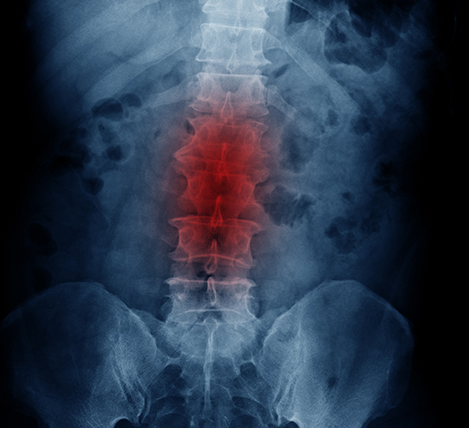

척추관 협착증은 단순히 허리가 아픈 질환으로 오해받지만, 신경이 지나가는 통로가 좁아져 다리 저림이나 보행 장애로 이어질 수 있습니다. 특히 중장년층에게 자주 나타나며, 장시간 앉아 있거나 잘못된 자세로 인해 증상이 점점 심해지는 경우도 많습니다. 이 글에서는 척추관 협착증 운동법과 함께, 실제로 많이 궁금해하는 척추관 협착증 수술비용까지 현실적으로 정리했습니다.

척추관 협착증은 말 그대로 척추관, 즉 신경이 지나가는 공간이 좁아지는 상태를 말합니다. 나이가 들면서 디스크가 퇴행하거나, 뼈와 인대가 두꺼워지면서 신경을 압박하게 되는 것이 일반적인 원인입니다. 이로 인해 허리 통증뿐 아니라 엉덩이, 허벅지, 종아리까지 저릿하거나 걷기 어려워지는 증상이 나타납니다.